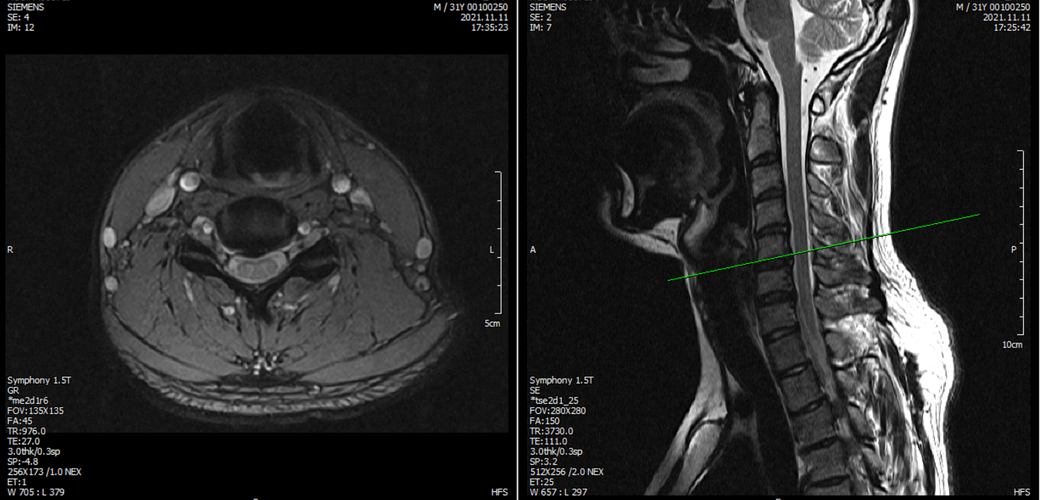

아래는 저의 경추과 요추 MRI 사진 첨부합니다.

• 1번 째 사진

• 2번 째 사진

• 3번 째 사진

• 4번 째 사진